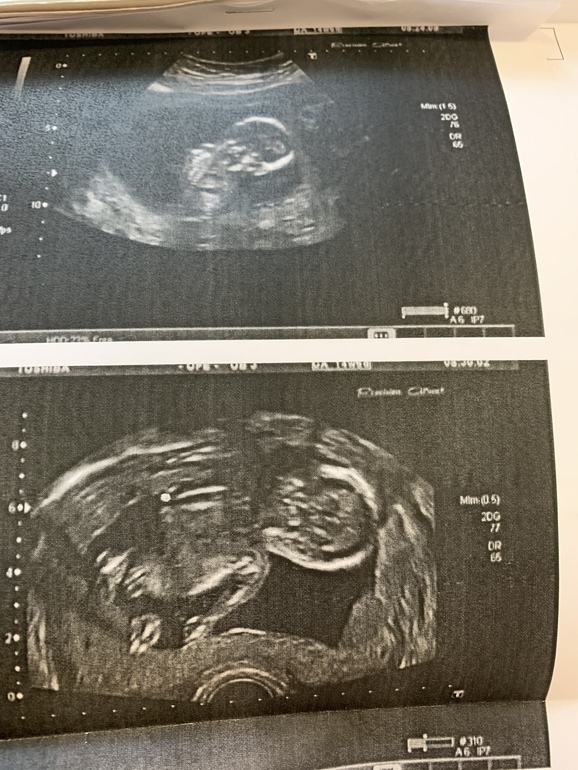

На первом УЗИ в 6недель и 5 дней ктр был на этот же срок , сейчас 24 неделя и 2 дня,а развитие ставят на неделю больше и пишут крупный плод. Сказала узист ,что он просто большой,но и мы не маленькие у меня рост 180 , а отец в ширину сам по себе крупный ....

может ли такое быть ,что ктр соответствует сроку день в день , а вес больше примерно на неделю -две?

Сделали узи, а я не могу разобрать где и что, и вообще передом он или задом( руку, голову и туловище я в принципе вижу) 🤣